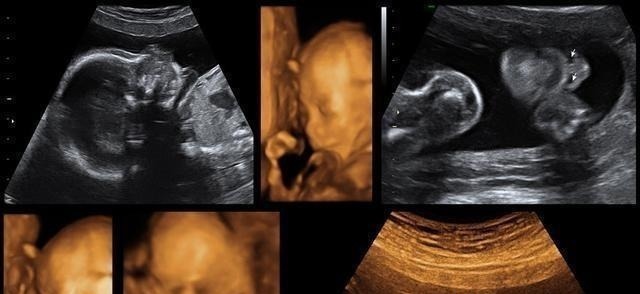

在怀孕之后那么四维大排畸检查是整个孕期非常重要的一个检查项目,在怀孕20周到18周的时候,除了能够筛查一些比较显著的畸形外,还能够看到宝宝人生中第1张照片,但我在做四维的时候妈妈是很激动的,有的妈妈在做四维的时候一次就成功了,那么有的宝宝可能就会不配合,就做了好几遍。

为什么宝宝做四维的时候不愿意动呢?宝宝处于睡眠时间,其实宝宝的生物钟和大人也会处于一个不同的状态,如果是在做四维的时候,宝宝正在睡觉的时间,那么也就会不愿意动了。宝宝性格比较安静,其实我有一个闺蜜的宝宝在整个孕期也是不爱动的,然后胎动也不多,他就非常的害怕,就及时的去做了,产检也是很正常的,可能是胎动比较轻微,自己也并不是非常的敏感,所以说你就会感觉不到。宝宝比较害羞,毕竟这一次是和爸爸妈妈的,第1次见面,宝宝也就没有做好准备,可能就会比较害羞一些,那么宝宝也就会拿着小手遮住小脸,这样的话医生也就没有办法看清变不了,所以说是需要宝宝动一动才能够看清全貌的。